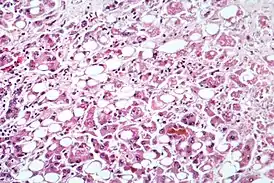

![]() Микрофотография клеток печени, поражённой алкогольным гепатитом | |